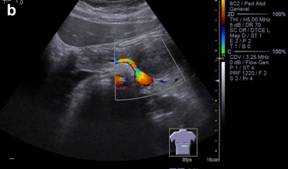

A 13-year-old boy referring postprandial fullness and nausea for the past three months. Weight loss and pain in the upper quadrants of the abdomen recently occurred. Blood workup, including tumor markers, was unremarkable. Abdominal ultrasound (Figure 1) showed a well-circumscribed heterogeneous hypoechoic mass in the region of the pancreatic body/tail. Unenhanced CT (Figure 2) confirmed the pancreatic lesion with a slightly heterogeneous density. No calcifications were identified. T2-weighted MR images (Figure 3ab) showed a 4.8 cm heterogeneously hyperintense lesion in the pancreas, showing a hypointense rim. This rim was also hypointense on T1-weighted images (Figure 3c), consistent with the presence of a tumoral fibrous pseudocapsule. T1-weighted images also showed some internal areas of increased signal intensity compatible with hemorrhage.

Figure 2. Unenhanced axial abdominal CT scan: hypodense, slightly heterogeneous mass of the body/tail of the pancreas, without calcifications. |

On ultrasound, solid pseudopapillary tumor presents as a well-circumscribed heterogeneous mass surrounded by a pseudocapsule of compressed pancreatic tissues and reactive fibrosis, sometimes with central cystic areas of necrosis [6]. The capsule may be visualized as an echogenic or, less commonly, hypoechoic rim at ultrasound and typically hypoattenuating at CT [4]. Unenhanced CT may identify hemorrhage and tiny calcifications [6, 7].